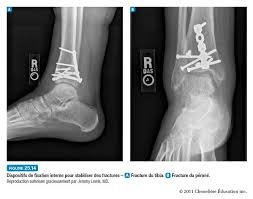

La fixation interne est l'une des techniques chirurgicales permettant de réduire une fracture complexe ou instable. Elle consiste à insérer de longues broches ou vis à travers la peau et dans l'os au-dessus et au-dessous du site de la fracture. Ces broches ou vis doivent être maintenues en place au moyen d'un appareil externe composé de brides, de tiges et de barres qui forment un cadre autour de la fracture tout en rapprochant les fragments. L'appareil est retiré une fois que l'os est guéri.

Certaines fractures requièrent une réduction ouverte et une fixation interne. Le cas échéant, le chirurgien pratique une incision cutanée au niveau de la lésion et se sert de divers instruments chirurgicaux pour reconstruire et repositionner les fragments de sorte de manière optimale. Avec des instruments spécialement conçus pour la manipulation des fragments, le chirurgien réaligne et fixe les fragments du corps de l'os l'un contre l'autre en utilisant, selon le cas, des fils, des broches, des vis, des tiges et des plaques métalliques. L'intégrité structurale de l'os peut être restaurée en insérant des tiges faites d'acier inoxydable, de titane ou d'autres alliages dans la cavité où se trouve la moelle; deux fragments osseux de grandes dimensions peuvent être maintenus ensemble au moyen de plaques métalliques profilées et vissées à travers la surface de l'os; d'autres fragments sont assemblés par des fils ou des clous.